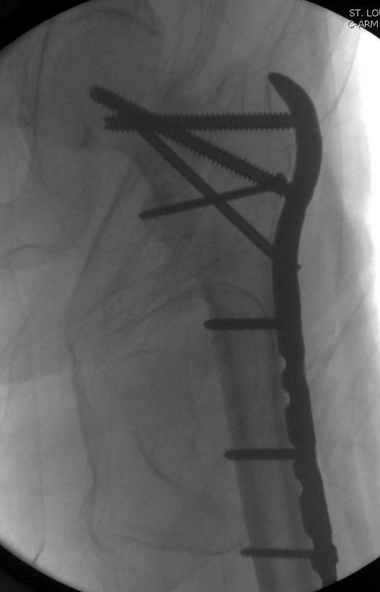

Re: [1/3] Перелом проксимального бедра

Применили проксимальную Synthes Locking plate, из-за множественных фрагментов посчитали более приемлемым в этом случае (клиника университетская, резиденты должны имет возможность созерцать разные варианты остеосинтеза).

Также старался минимизировать доступ на уровне перелома с субвастус доступом, диафиз фиксирован перкутанно, не стали гонятся за малым вертелом, как смог зафиксировал.

Перелом из четырех фрагментов, не стабильный (лекция Michael R. Baumgaertner, http://www.hwbf.org/ota/bfc/baumg/exp.htm), нужна стабильная фиксация.

Фиксация таких нестабильных чрезвертельных и reverse obliquity субтрохантерик переломов всегда была сложной задачей и ранее использовали Blade Plate. Но многие локальные общие ортопеды, к которым, в основном поступают такие больные, имели трудности с применением импланта, где необходимо было точная калькуляция по введению Blade и поэтому Synthes разработал Proximal Locking plate как альтернативу, где три проксимальные шурупа в разных направлениях создают концепцию угловой стабильности Blade Plate.

Со второго дня движения в суставе, контрольный осмотр через две недели и в зависимости от рентгенологического сращения, дозированную нагрузку с постепенным увеличением начнем через 5-6 недель.